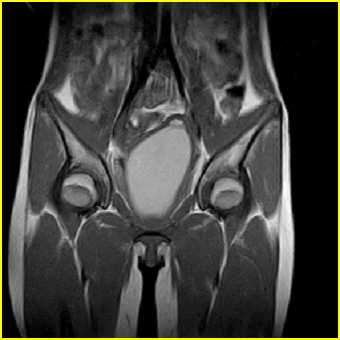

女、15岁、下腹疼痛2天,排尿困难1天。查体:处女膜闭锁,距处女膜约4至5cm处扪及一约5cm直径的圆形包块,张力较高,触痛明显、欠活动。b超提示子宫增大伴宫内增强回声团。

影像意见:子宫直肠陷凹积血。

更正影像意见:阴道积血。

处女膜闭锁,阴道积血

处女膜闭锁,阴道积血,子宫积血.

先天性处女膜闭锁,伴阴道积血,不除外先天性阴道粘液囊肿形成。

阴道积血,子宫积血.

子宫及阴道积血。

处女膜闭锁,伴子宫及阴道积血.